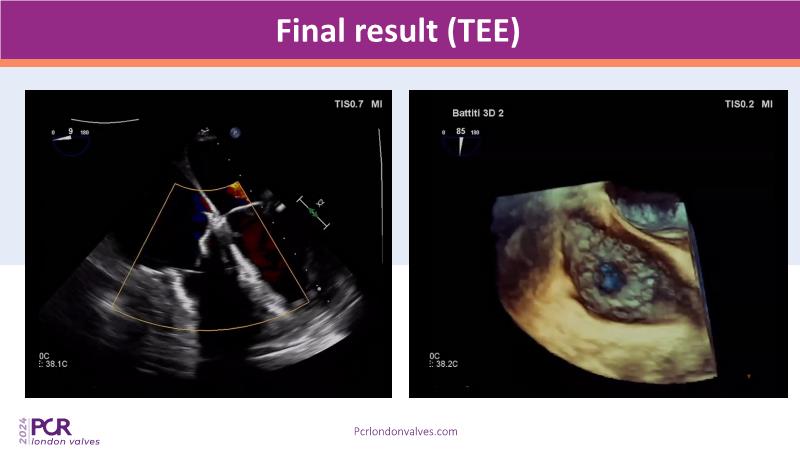

Join us as we explore the latest advancements in transcatheter tricuspid valve replacement technologies. This session develops the anatomical and imaging challenges associated with this rapidly developing clinical field and provides an update on the Cardiovalve tricuspid clinical program, illustrated by a recorded case.